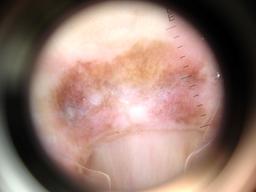

{

"age_approx": 65,

"anatom_site_general": "upper extremity",

"anatom_site_special": "acral NOS",

"concomitant_biopsy": true,

"dermoscopic_type": "contact non-polarized",

"diagnosis_1": "Malignant",

"diagnosis_2": "Malignant melanocytic proliferations (Melanoma)",

"diagnosis_3": "Melanoma in situ",

"diagnosis_confirm_type": "histopathology",

"family_hx_mm": false,

"image_type": "dermoscopic",

"mel_thick_mm": "0.00",

"melanocytic": true,

"patient_id": "IP_3069248",

"personal_hx_mm": false,

"sex": "male"